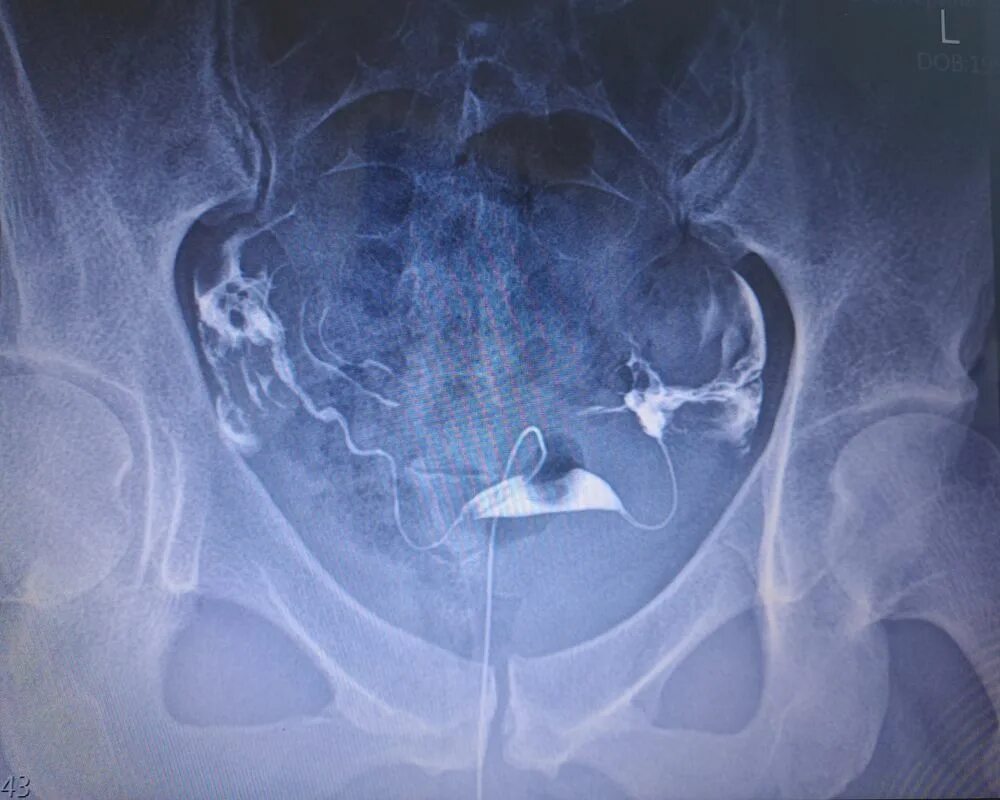

Ретрофлексия матки что это такое